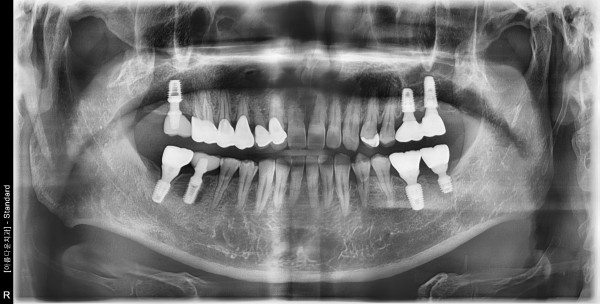

51세남자 우측상.하악 구치부 뼈이식및임플란트식립